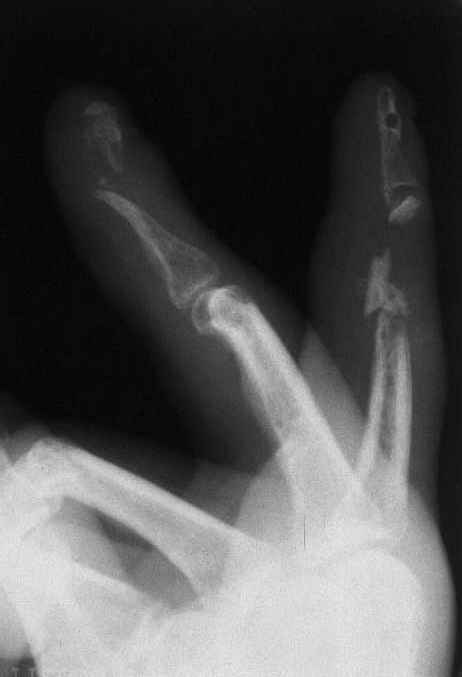

33 yo male motocross rider crashed after a jump sustaining isolated bilateral femur fxs, R side with a basicervical femoral neck and ipsilateral mid-distal 1/3 shaft, L side with a subtroch/prox 1/3 femur fx. Pt was HD stable, no LOC, GCS - 15, No other injuries, spines cleared.